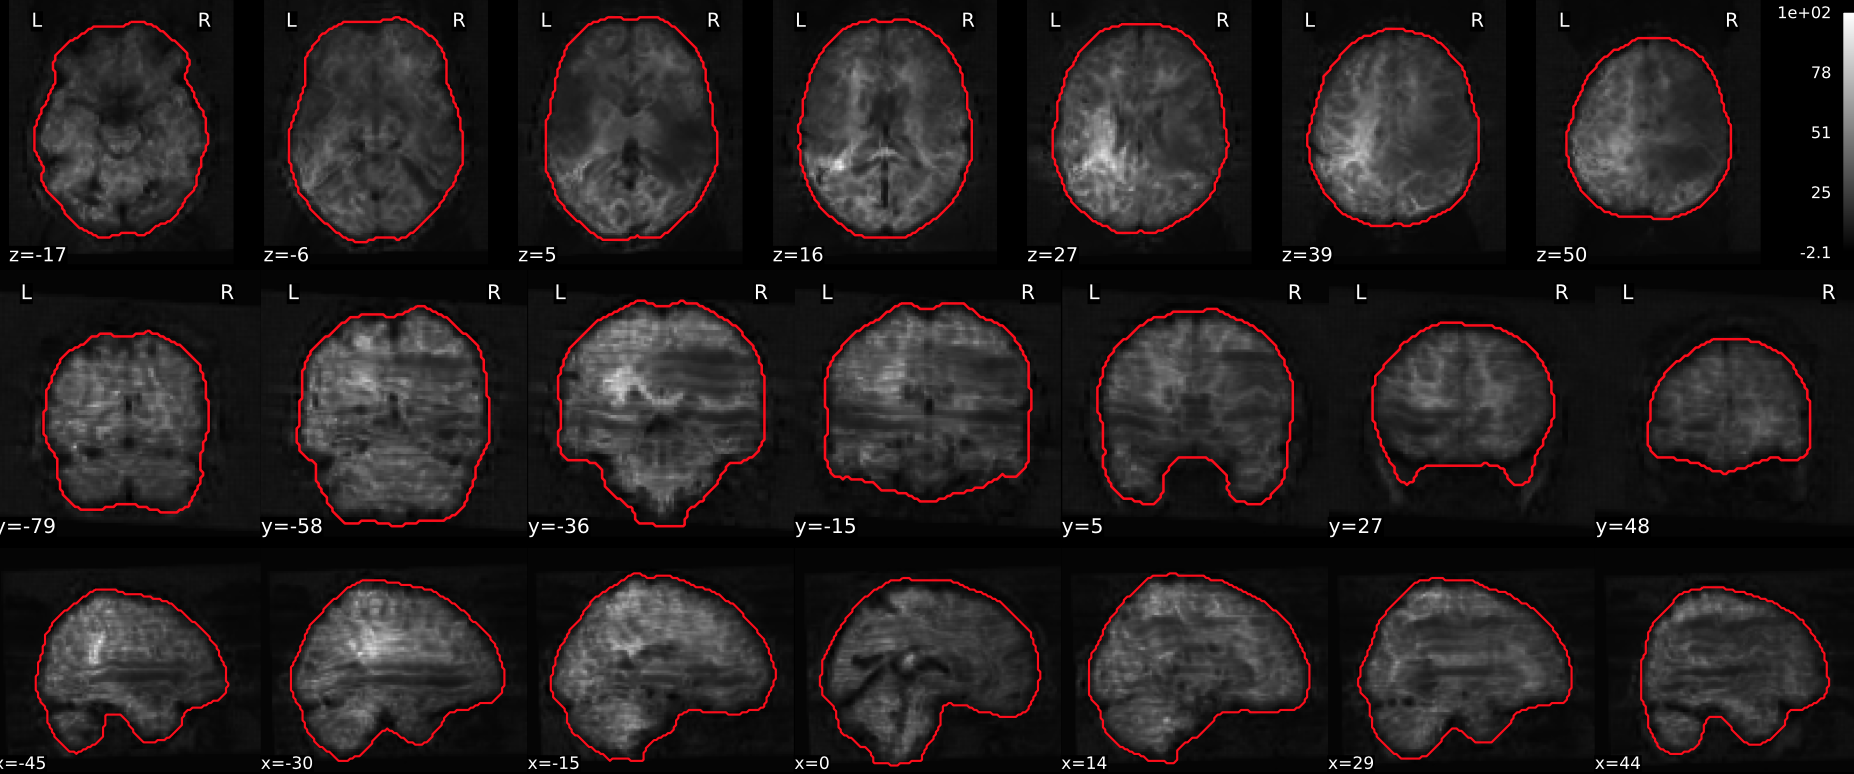

T1w skull stripping

Skull stripping is the process separating the brain (cortex and cerebellum) from the skull. The red line follows the outline of the brain and it separates it from the skull.

Example of a good subject

- There are no skull stripping errors, such as portions of the brain missing, or too much of the skull retained

- The red line follows the outline of the brain

Example of a bad subject

- There are skull stripping errors, such as portions of the brain missing, or too much of the skull retained

- NOTE: check all the images (slices) in the report. If only one image (slice) looks problematic, it is possible that the subject is okay and it is just a visual issue in that particular screenshot

Summary

| Good | Bad |

|---|---|

| The brain is fully inside the red line | Structures like the cranium or the eyes are inside the red line |

| No important brain structures are outside of the red line red line follows the natural outline of the brain | Important brain structures are missing inside of the red line |

-> if only one slice is problematic, it could be an issue related to the visual depiction of the data instead of an issue related to the test subject